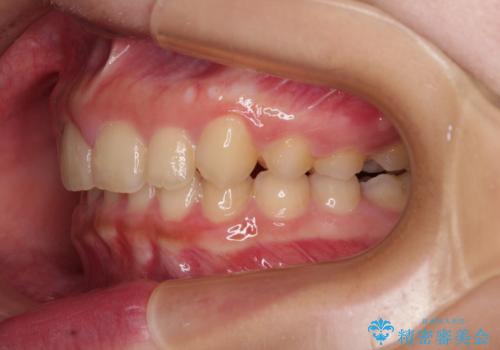

飛び出した前歯をインビザラインですっきりと

- 深い咬み合わせと上顎前歯の突出感を気にして来院された患者様です。

当院では通常、臼歯の咬合が理想的な位置に対して上顎が前方位にある場合。ワイヤー矯正または補助装置の併用したインビザライン矯正を選択しています。

今回は、できるところまででいいのでインビザライン単体で治療をしたいという希望があったため、インビザラインにて矯正治療を行うこととしました。

正面や横からの写真ではきれいに治っており、患者様は大変満足のいく仕上がりとなりましたが、深い咬み合わせの改善は不十分で、奥歯の咬み合わせも改善させることができませんでした。

インビザラインは、咬合力の強い方ですと、奥歯が歯肉内にめり込んでしまうため、前歯が強く接触してしまうことがあります。

こちらの方は、奥歯はしっかりと噛んだのですが、歯肉にめり込んでしまったことで、歯肉が腫れやすくなってしまいました。